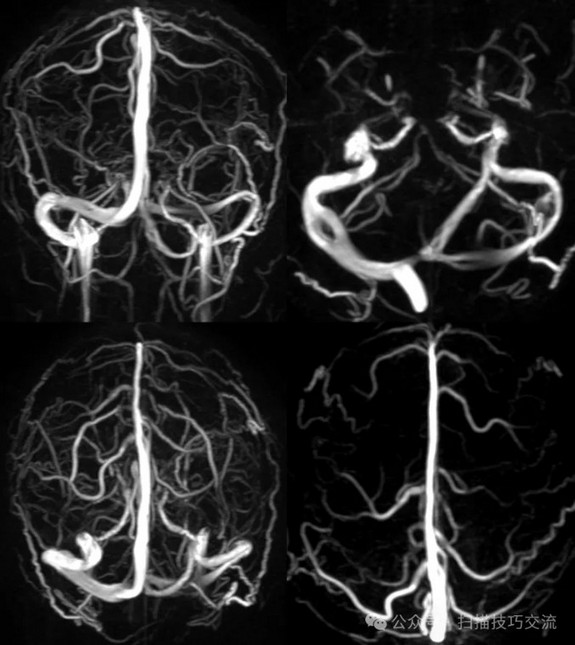

•汗腺分泌:正常,皮肤划痕正常反应。 •尿便障碍:无。性功能障碍无。 •专科情况:正常。不逐一罗列。 •辅助检查:01-05颅脑CT提示:1,上矢状窦、双侧横窦密度较高,请结合临床,必要时进一步检查;2,双侧脑室后角可疑稍高密度影,右顶叶局部脑沟密度可疑增高,建议进一步检查。 •初步诊断:静脉窦血栓

临床申请:颅脑平扫,静脉成像,磁敏感成像,颅内静脉血管黑血成像。

PC-MRV未见异常。